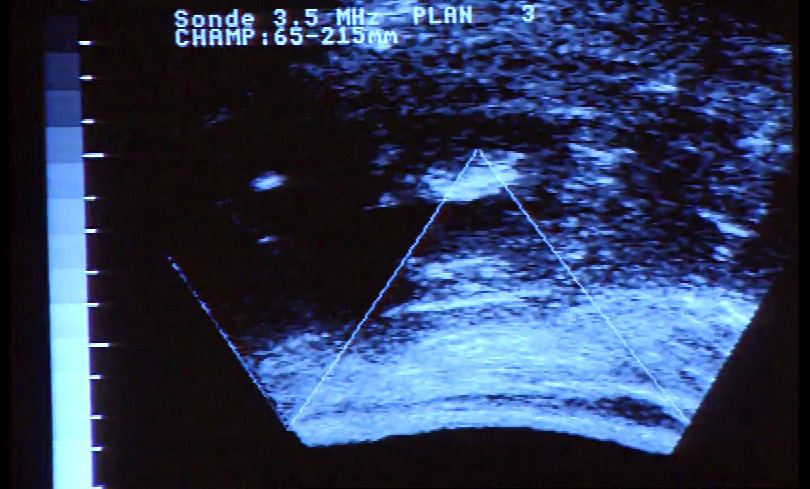

A complexidade das funções do fígado, os hospitais pediátricos, e os problemas causados pelas varizes, são os temas do programa. Na rubrica "Efeméride" é assinalado o nascimento do Professor Hernâni Bastos Monteiro.